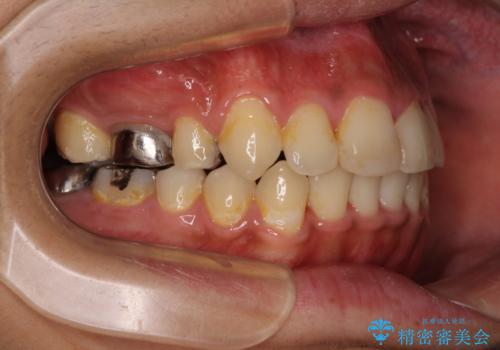

八重歯と開咬 ワイヤー装置での抜歯矯正

骨格的に下顎骨が上顎骨に対して後退位であったため、上顎の左右第一小臼歯を抜歯し、デコボコを改善するとともに開咬を改善していくこととしました。

舌の突出癖により開咬となっていたため、突出癖改善のためのトレーニングをしっかりと行っていただき、予定の期間で無事に治療を終えることができました。